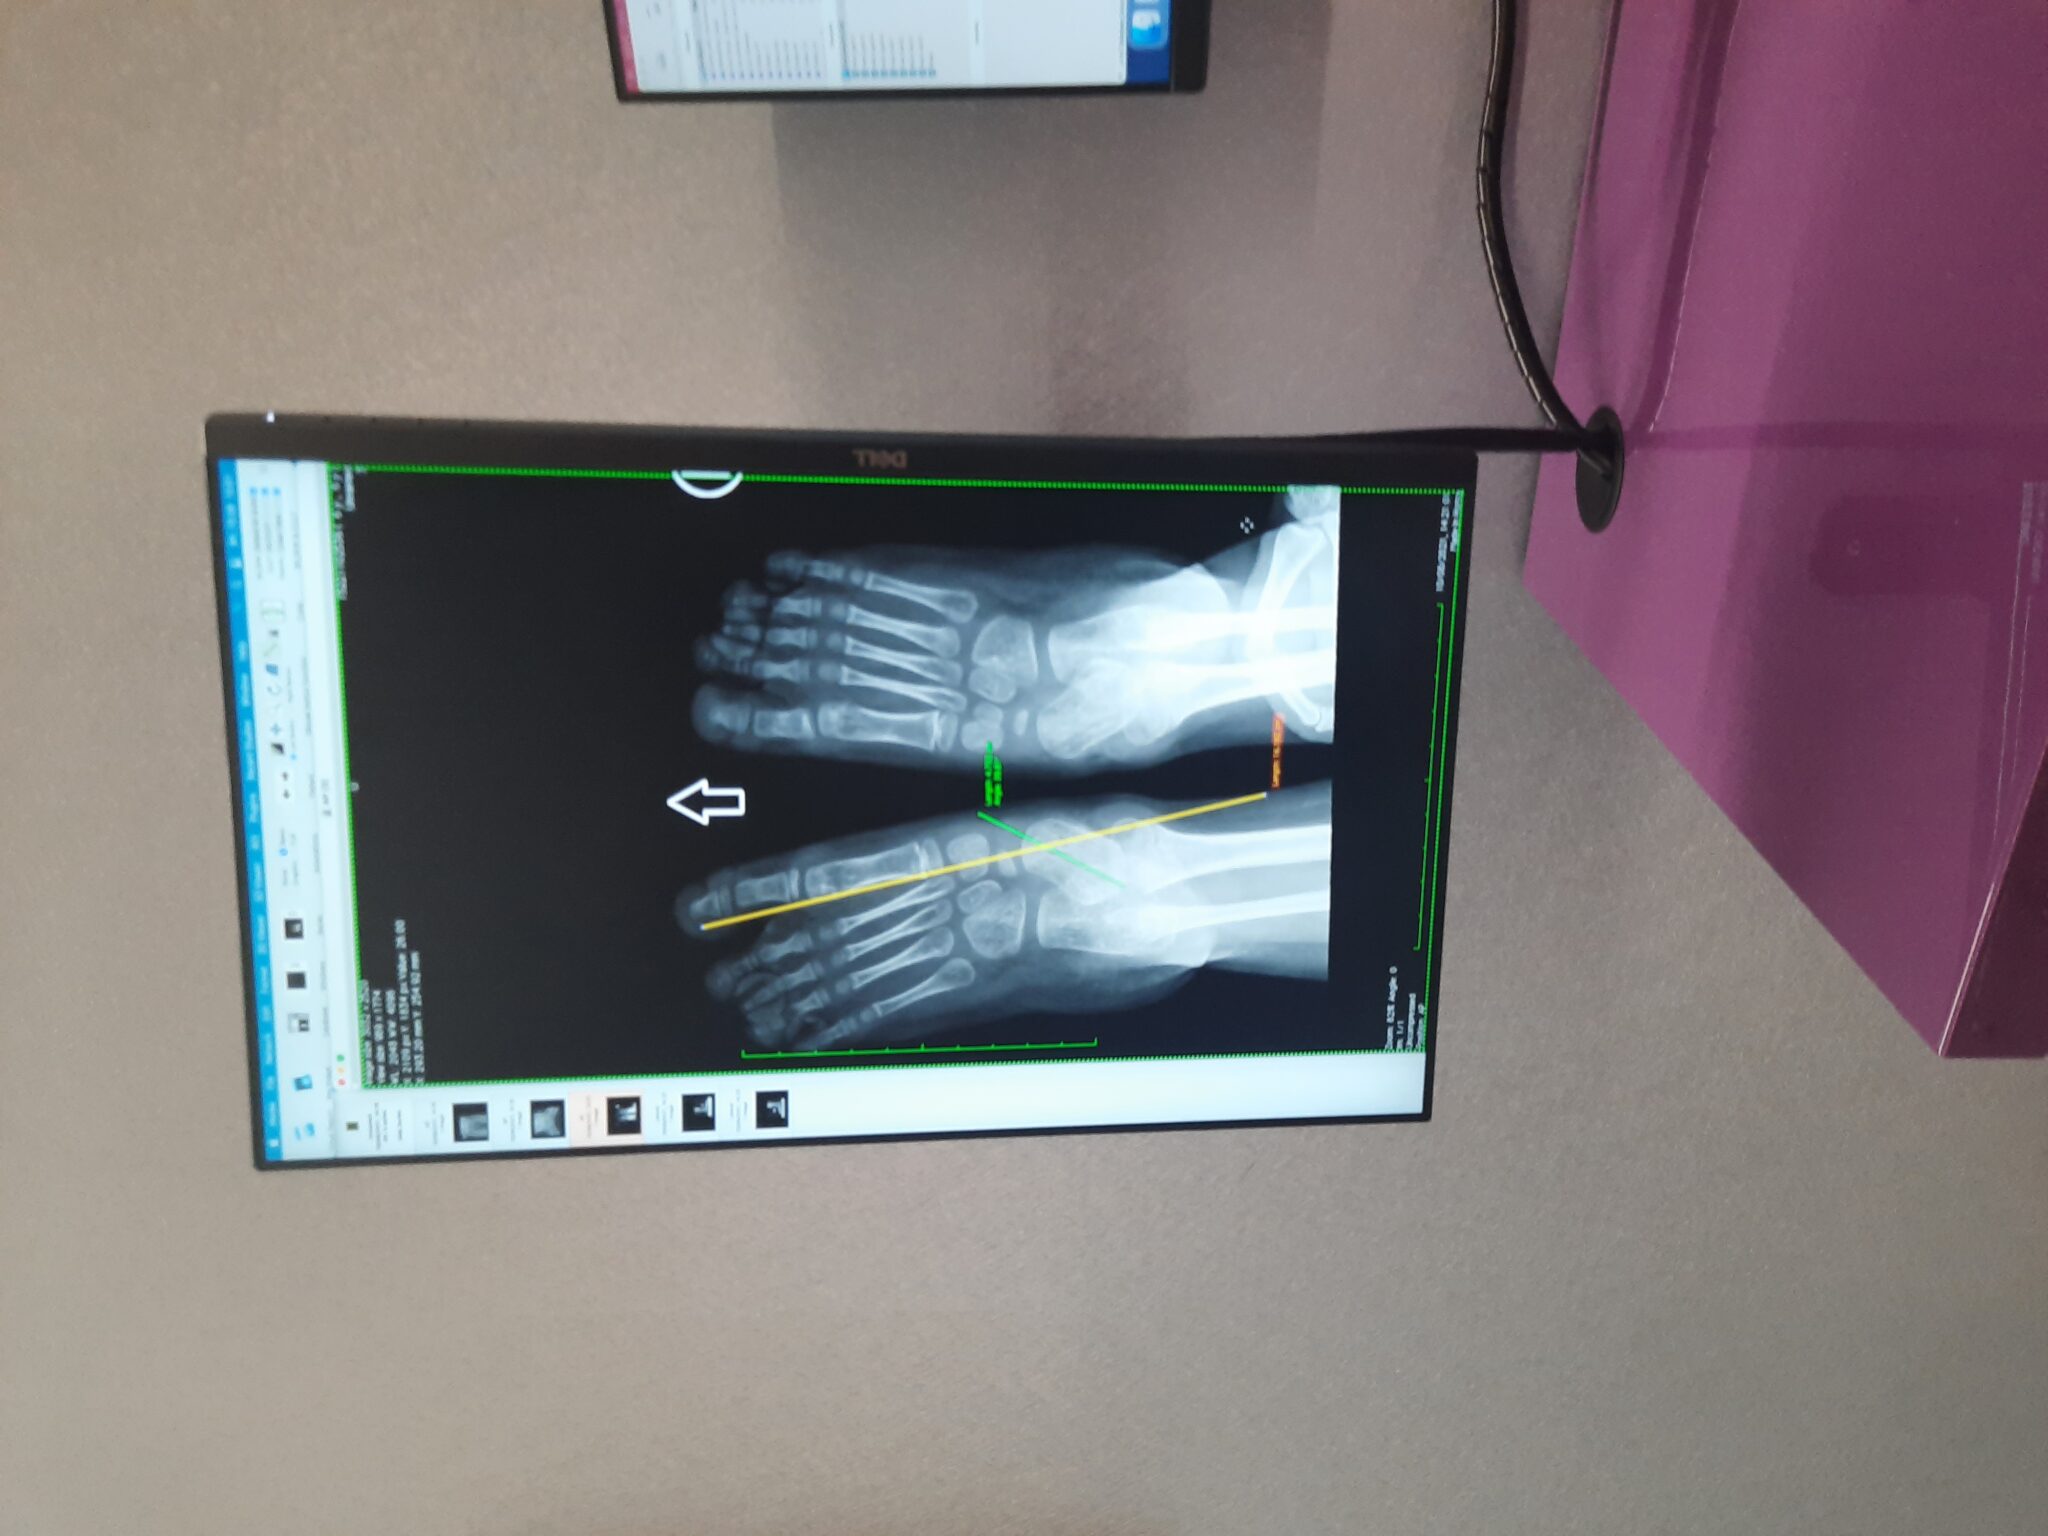

Krzyś w maju 2023 roku przeszedł operacje obu nóżek w Instytucie

dr. Paleya.